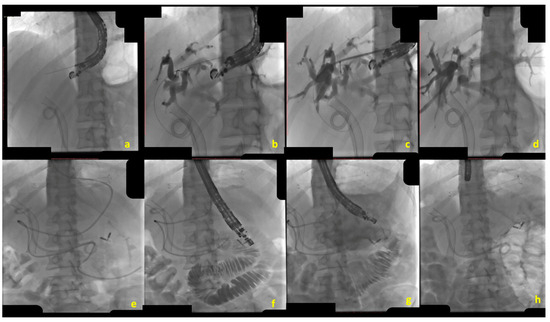

EUS-CDS consists of creating a bilio-digestive anastomosis between the common bile duct (CBD) and the duodenum [12] (Figure 1).

Under EUS guidance, from the duodenal bulb, the dilated CBD (>12 for expert operators, >15 mm for non-expert operators) was identified with the EUS scope in a “long” position, with the tip of the endoscope in the direction of the hepatic hilum [19]. At this stage, a bilio-digestive anastomosis is created by advancing an electrocautery-enhanced LAMS (ec-LAMS) directly into the CBD lumen under EUS guidance. While EUS-CDS can theoretically be performed without fluoroscopic assistance, in cases of a small-diameter CBD, the free-hand technique may be replaced with the over-the-wire technique [20]. This approach involves initially puncturing the CBD, preferably with a 19-gauge FNB needle, followed by the advancement of a guidewire into the CBD and performing a cholangiogram to confirm accurate access. The ec-LAMS catheter can then be advanced over the wire into the CBD, allowing for precise deployment of the LAMS. Indications from international societies (ESGE, ASGE) have evolved during the last couple of years. In 2022, the ESGE guidelines recommended EUS-CDS over EUS-HGS as the preferred technique for managing dMBO, citing a lower rate of adverse events (AEs) associated with EUS-CDS [13]. However, subsequent evidence has provided conflicting data regarding the safety profiles of these two procedures. A meta-analysis and systematic review by Yamazaki H et al., published in 2023, analyzed 18 studies encompassing 972 patients and found no significant difference in AEs between EUS-CDS and EUS-HGS (OR 1.39; 95% CI 1.00–1.93) [21]. In contrast, a newer meta-analysis by Rizqiansyah SY et al., published a year later, included 11 comparative studies (both controlled and uncontrolled) with a total of 537 patients and reported a significantly higher AE rate in the EUS-HGS group compared to the EUS-CDS group [22]. Furthermore, growing evidence showed that EUS-CDS may be associated with a risk of ascending cholangitis in the case of concomitant GOO [23,24]. In this view, the ASGE guideline suggested EUS-HGS over EUS-CDS in case of duodenal malignant infiltration, pre-existing ES, or GOO proximal to the pylorus [15].